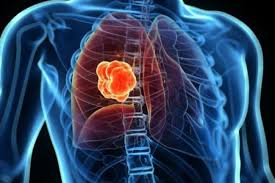

Secondary Lung Tumors In Dogs - Image Gallery Primary Metastatic Tumors Part 1 Clinician S Brief : The incidence of primary lung cancer, that is, lung cancer that is not occurring secondary to another cancer account only for about 1% of newly diagnosed tumors in dogs and cats.. Metastatic tumors in dogs are made up of cells of the original tumor, not the site in which they have moved to. Only about 1% of cancers in dogs are lung cancers. Pulmonary metastatic disease most commonly. Lung tumor, rather than a metastatic cancer that has spread to the lungs from another location in the body. There are chances though that the percentage may be higher, studies say.

Metastatic lung cancers (cancers that spread to the lungs from other locations) are much more common in dogs than primary lung cancers.

Metastatic tumors in dogs are made up of cells of the original tumor, not the site in which they have moved to. If your dog has metastatic neoplasia, you have to see a veterinary professional to find the primary tumor. The following diagnostics are recommended: There are two type of lung cancer diagnosed in dogs. Primary lung cancer, which is quite rare and metastatic lung cancer, spread from other areas of the body. Lung cancer in dogs and cats compared to people, primary lung cancer is very uncommon in dogs. Secondary metastasis to the lungs is more common than primary canine neoplasm. Pulmonary carcinomas have a high tendency to metastasize, so full. Most primary lung tumors are a type of cancer called carcinoma. Primary lung tumors are those that arise from the lungs, mostly from cells lining the bronchi. Usually there are no symptoms in the early stages of canine lung cancer. So, if a dog that first got cancer in their mouth for instance, or in their bones, they risk the chance of it metastasizing through the bloodstream to the lungs. The second kind of lung cancer in dogs is called metastatic lung cancer, which means the cancer originated somewhere else in the body, but has spread to the lung.